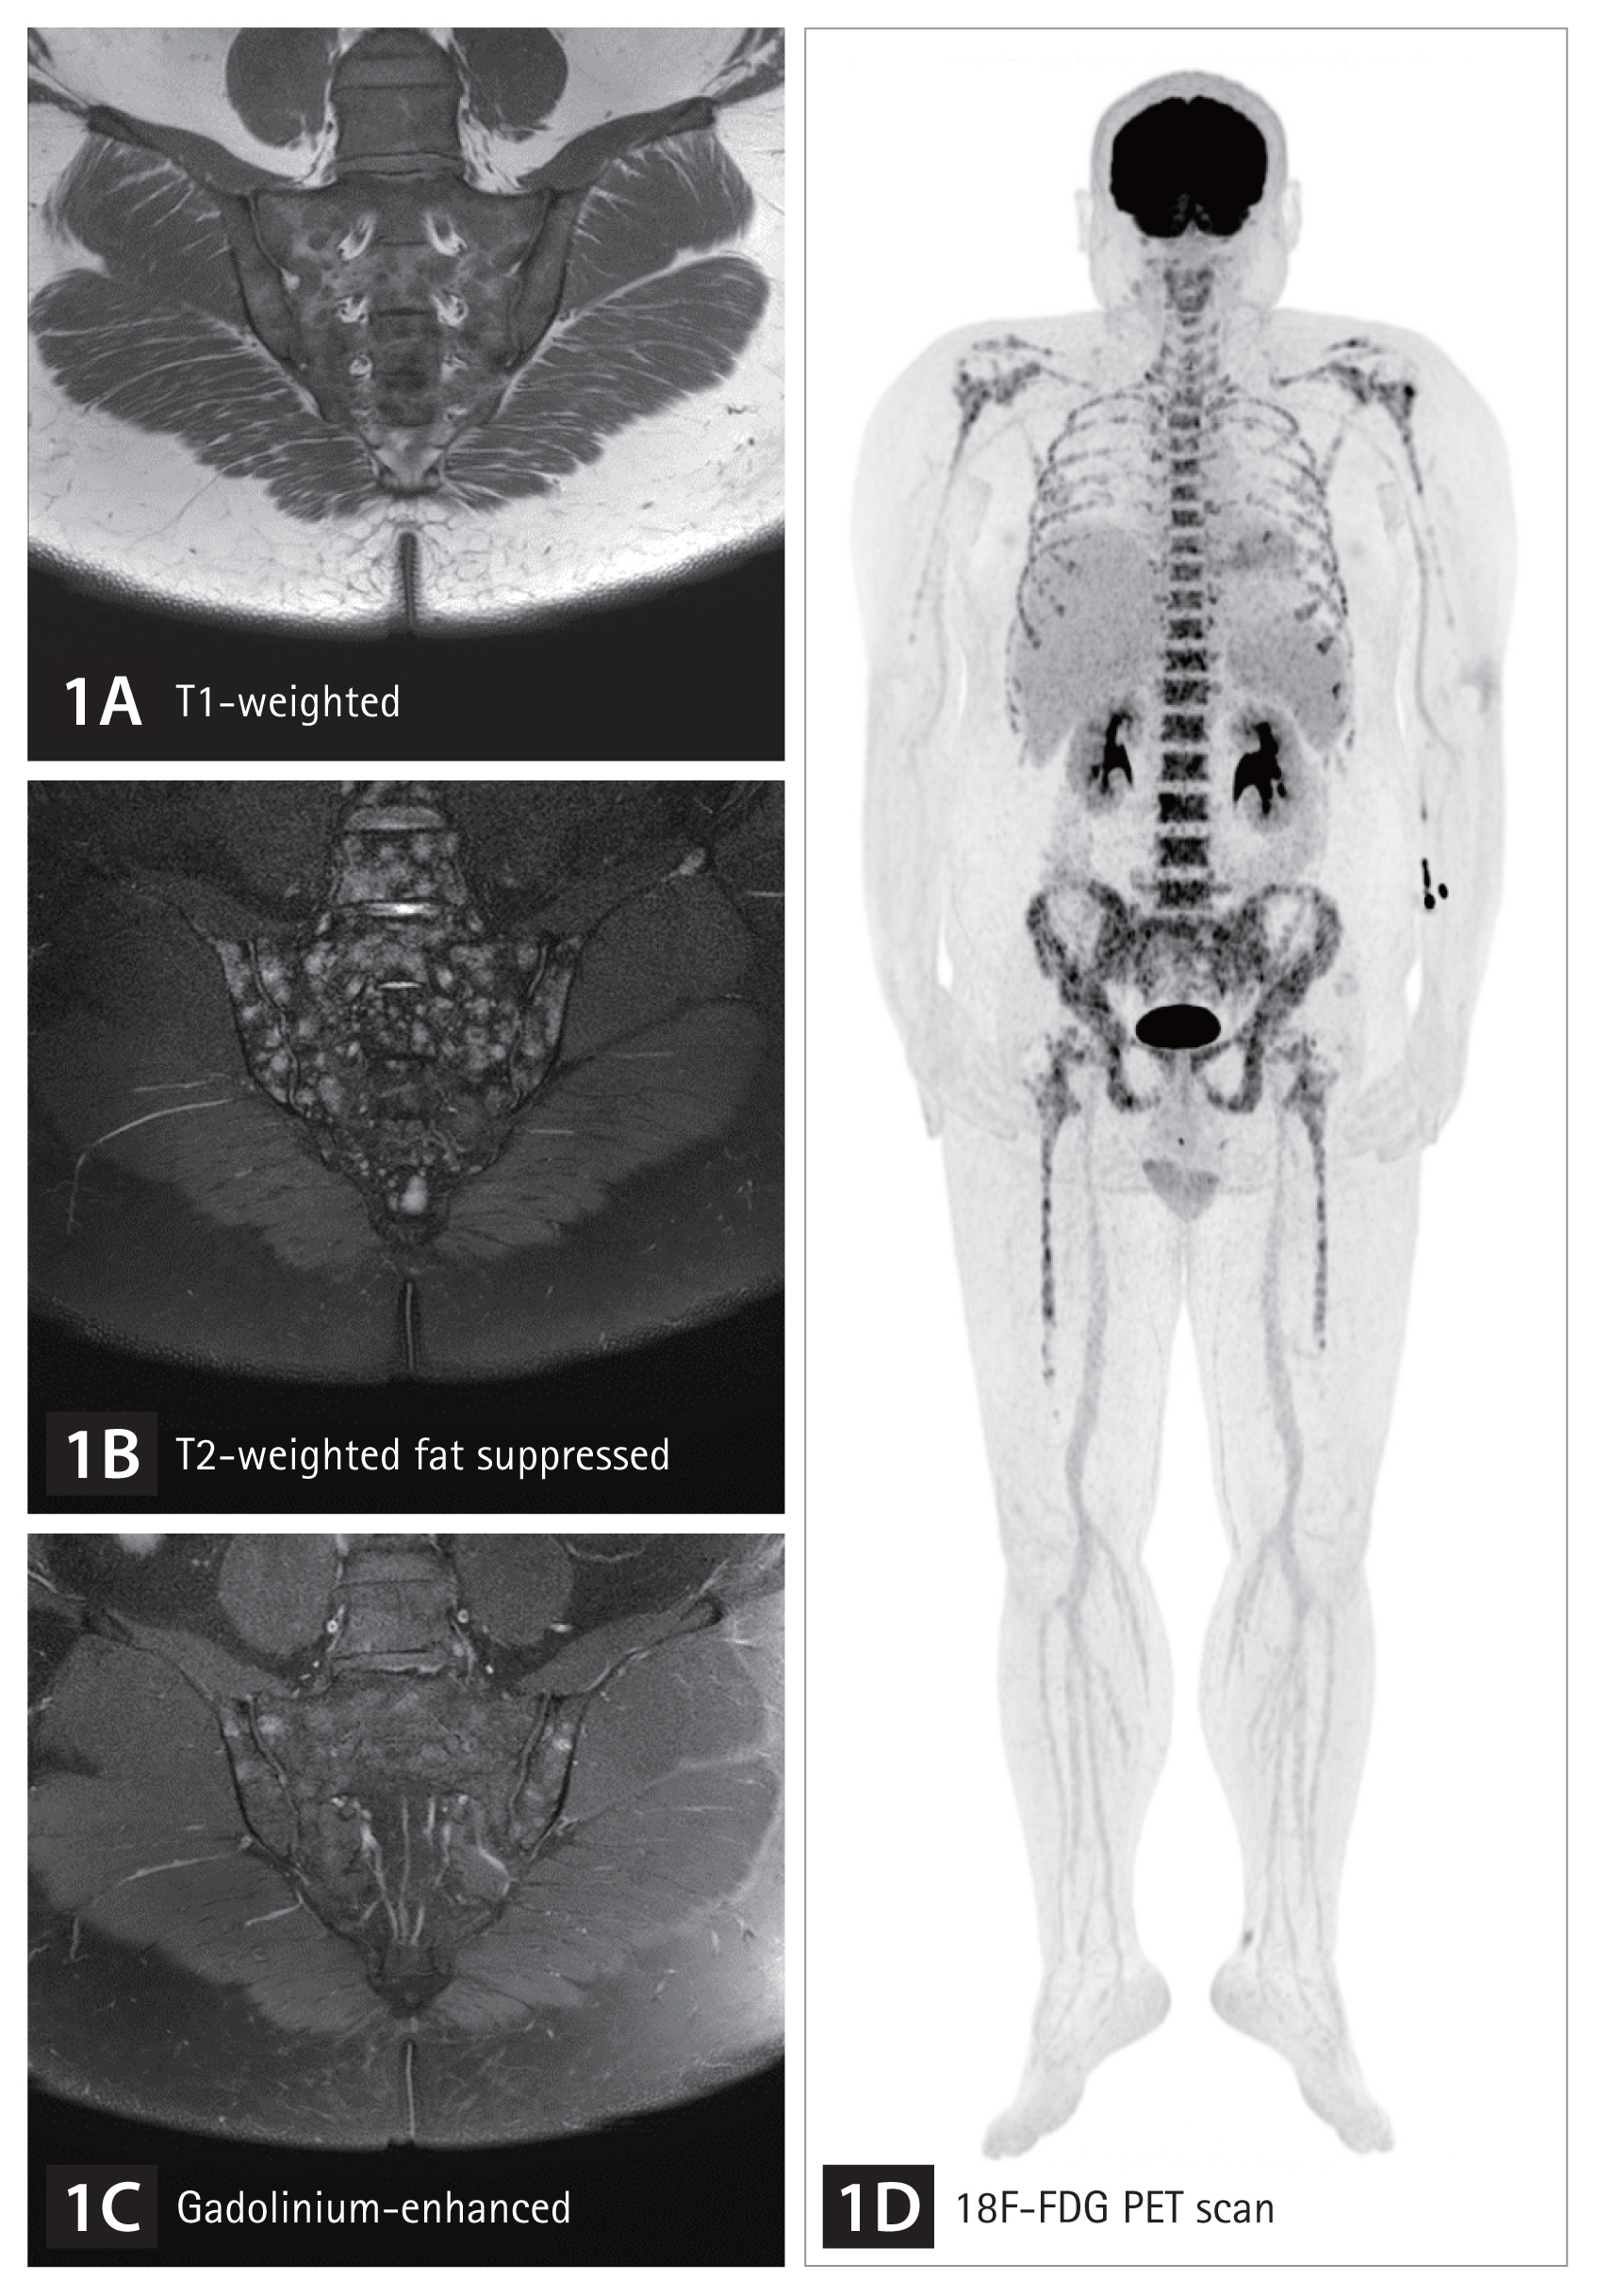

The patient reported worsening low back and pelvic pain over 3 weeks, unalleviated by rest and relieved by walking, particularly intensifying at night. Back pain hindered the Schober test, but sacroiliac tenderness was noted. Based on previous research indicating axial spondyloarthritis with unexplained fever [1], features of inflammatory back pain prompted diagnostic evaluation for axial spondyloarthritis. With a negative result for human leukocyte antigen (HLA)-B27 and absence of sacroiliitis on X-ray, magnetic resonance imaging (MRI) of the sacroiliac joint was conducted, revealing a myriad of small foci exhibiting low signal on T1-weighted images (Fig. 1A) and high signal on T2-weighted images (Fig. 1B), with nodular enhancement by gadolinium contrast (Fig. 1C). An 18F-fluorodeoxyglucose positron emission tomography scan also demonstrated hypermetabolic activity in the bone marrow of axial skeleton (Fig. 1D). Despite a normal peripheral blood smear, a bone marrow biopsy was performed, ultimately confirming B-lymphoblastic leukemia (Fig. 2).

Sacroiliac magnetic resonance imaging (MRI) and 18F-fluorodeoxyglucose positron emission tomography (PET) scan were conducted to assess inflammatory back pain in a 33-year-old male with unexplained fever. Unlike sacroiliitis, which is characterized by bone marrow edema in the subchondral bone, the MRI showed numerous small foci with a low T1-weighted signal (A) and high T2-weighted signal (B), along with nodular enhancement by gadolinium contrast (C). The PET scan also revealed hypermetabolic activity in the bone marrow of axial skeleton (D).